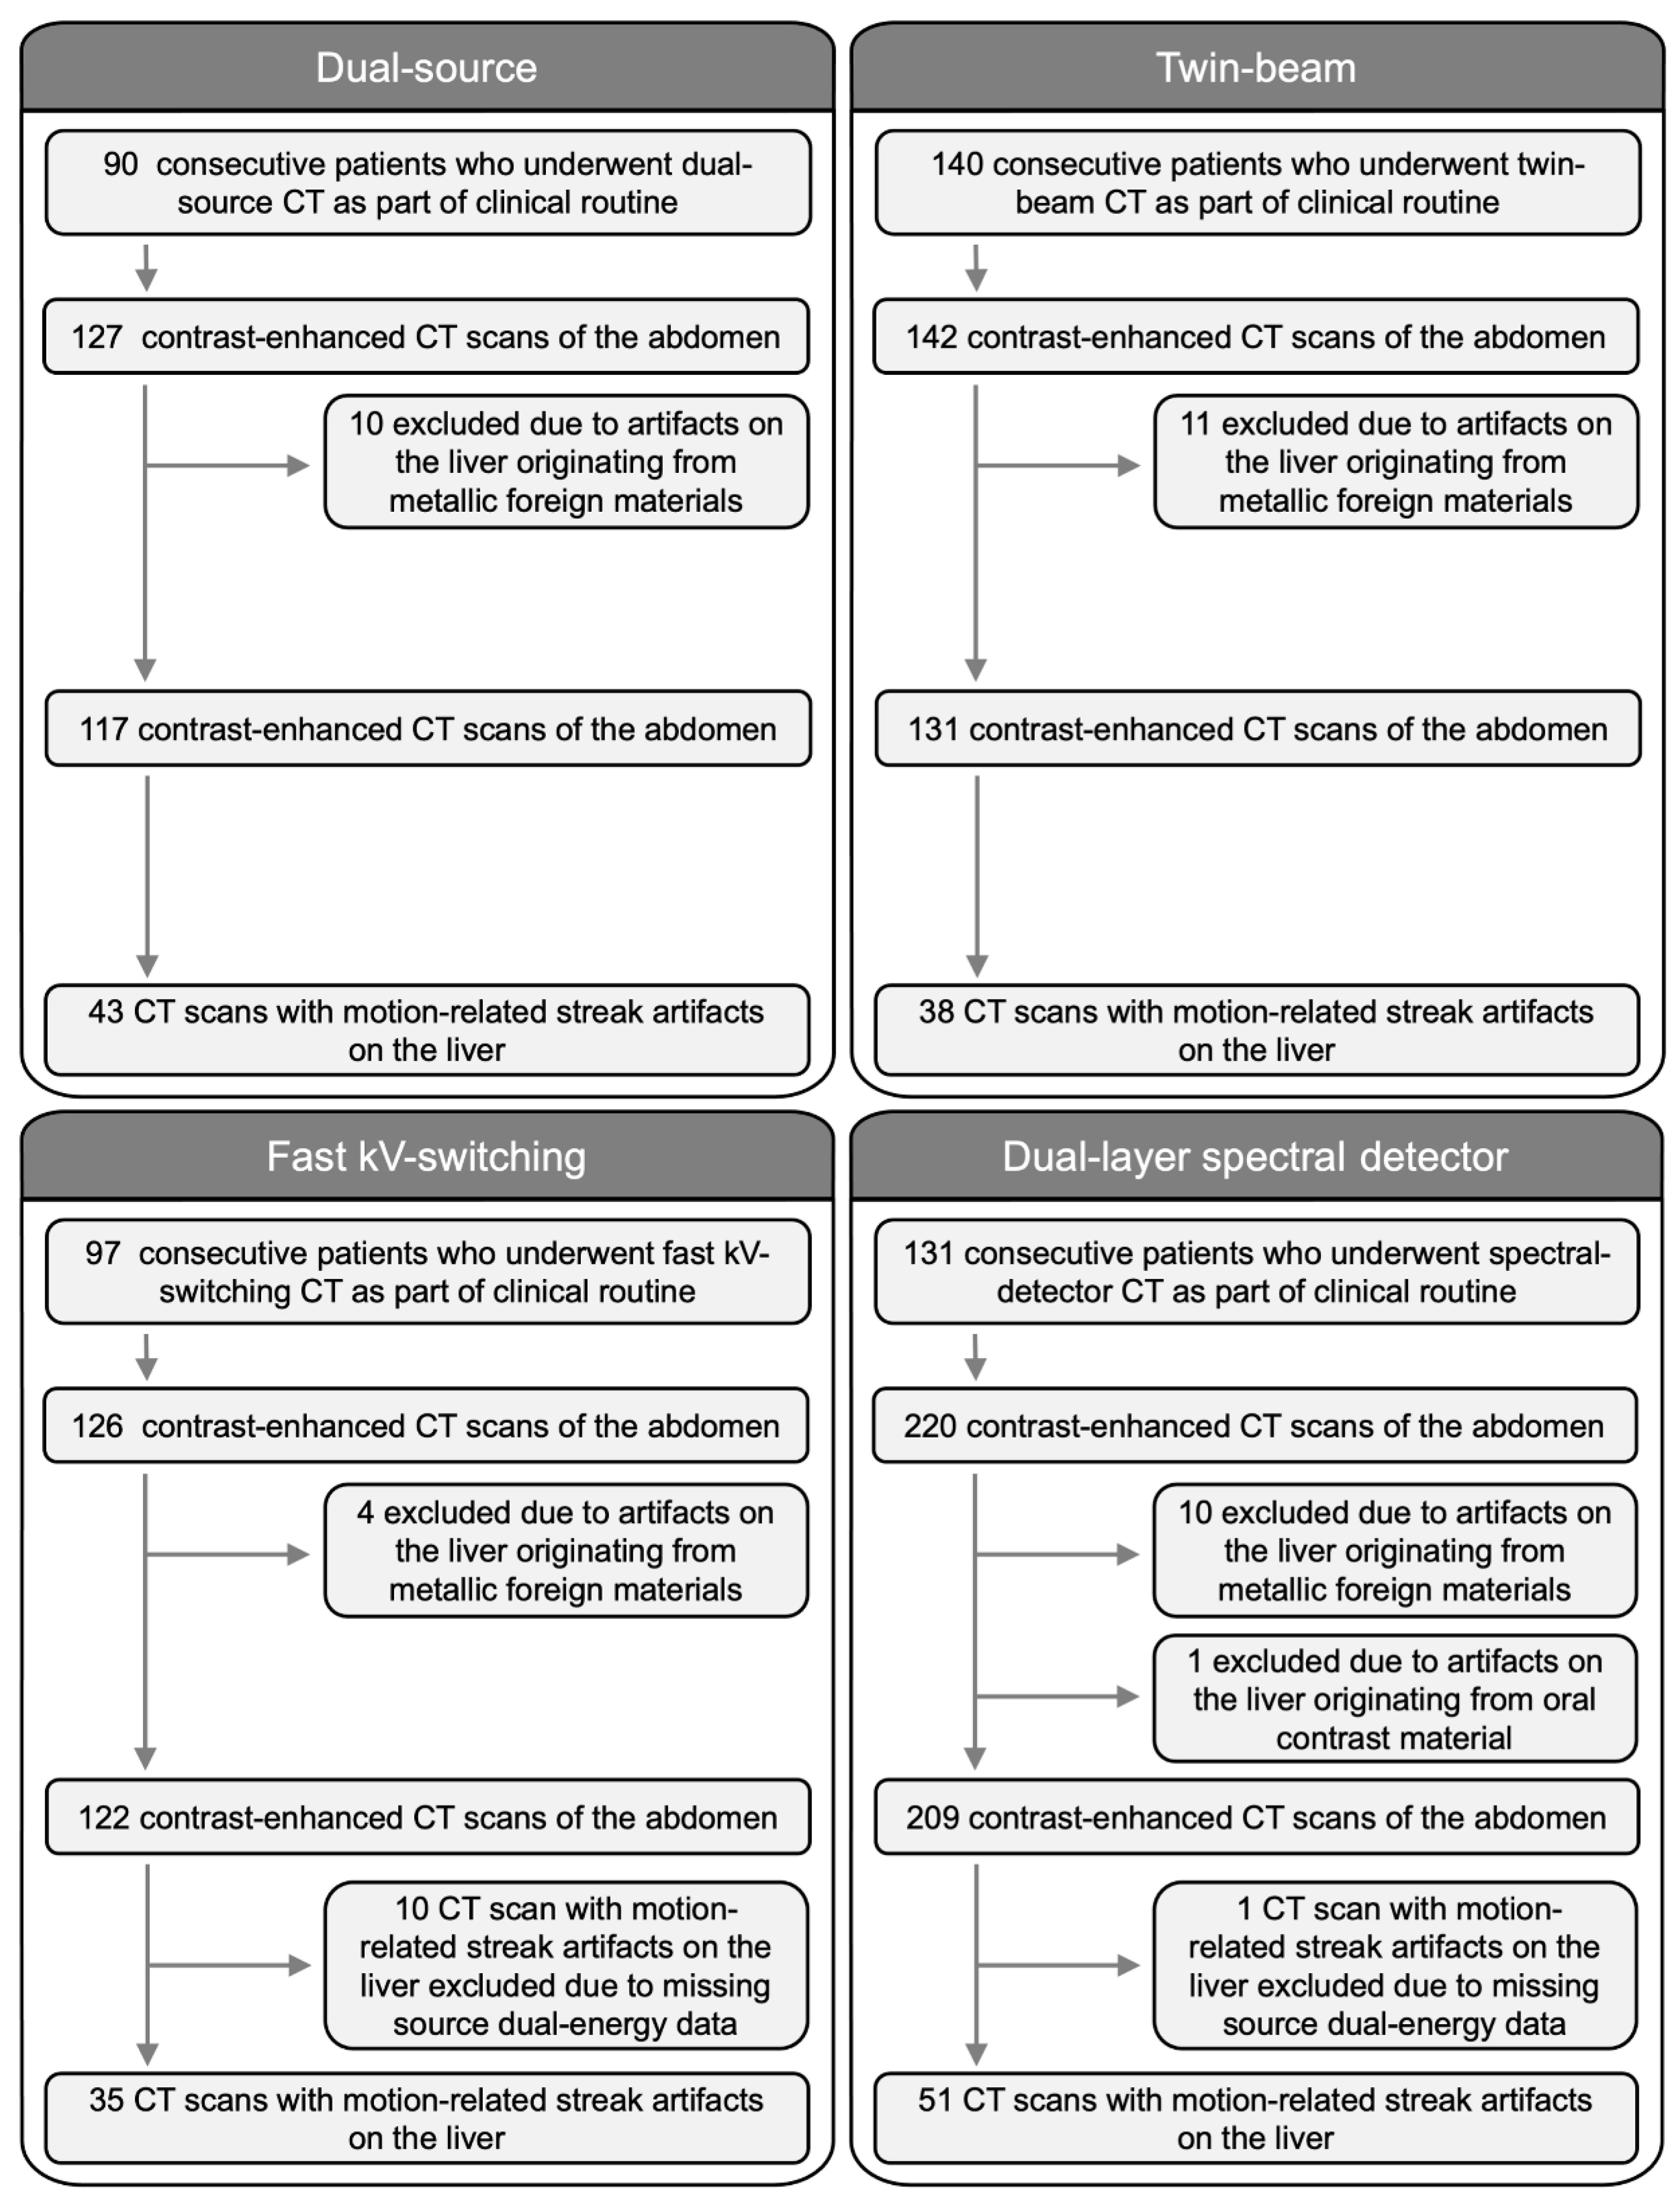

2.1. Study Population

3.1. Study Population